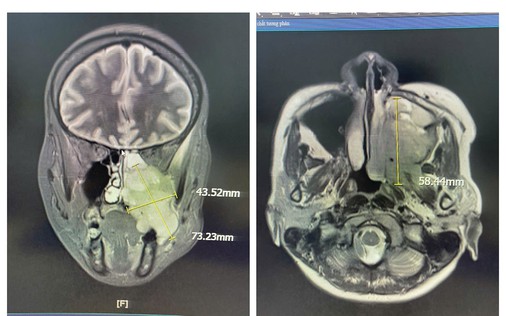

Tai nạn giao thông phát hiện khối u não hiếm gặp ẩn mình suốt 10 năm

Suốt gần 10 năm, chị S.C. (42 tuổi, ngoại quốc) nhiều lần trải qua các cơn đau đầu và mờ mắt thoáng qua nhưng không rõ nguyên nhân. Chỉ đến khi nhập viện kiểm tra sau một tai nạn giao thông mới bất ngờ phát hiện khối u não hiếm gặp - cho thấy căn bệnh đã âm thầm tồn tại trong thời gian dài mà không được nhận diện.